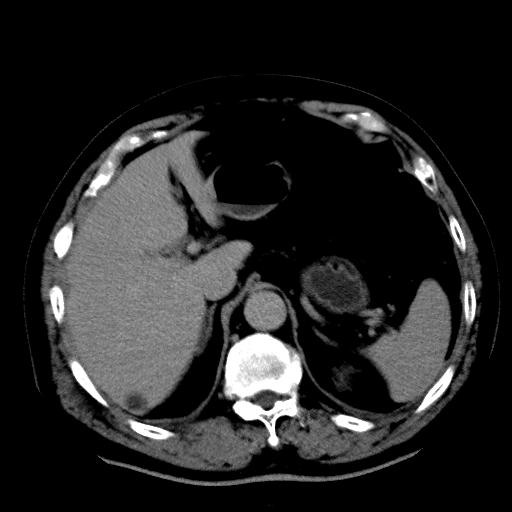

以下是引用zhctwbh在2008-8-23 14:20:00的发言:[br]囊肿合并出血

以下是引用zjb在2008-8-23 16:41:00的发言:[br]囊肿并出血可能性大。